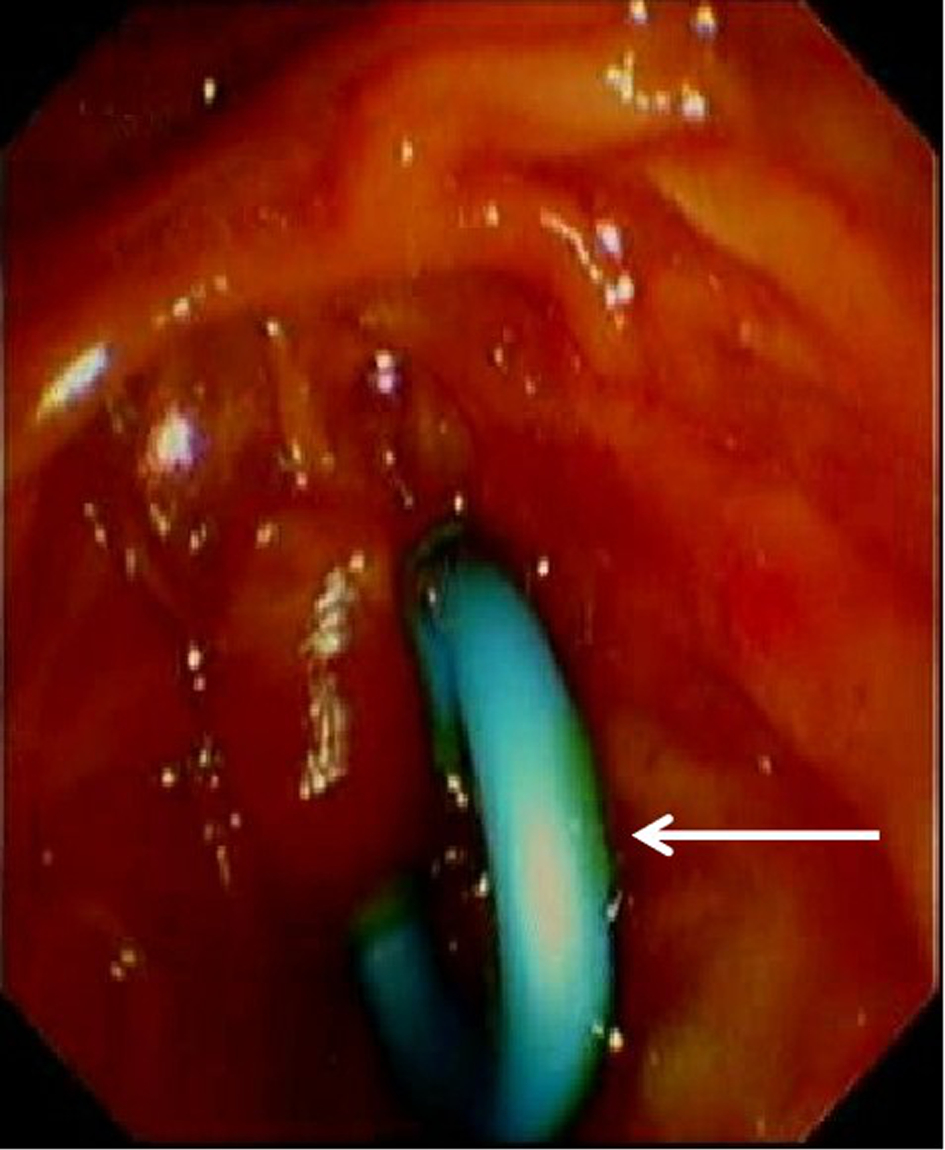

脓毒症合并自发性脾破裂出血1例报告

柳舟, 夏文芳, 詹丽英, 方小雨, 张亮, 詹娜, 禹荣, 黄丽, 朱垒

2023, 39(8): 1926-1931. DOI: 10.3969/j.issn.1001-5256.2023.08.024

摘要(1302) HTML (294) PDF (4249KB)(101)

摘要:

脓毒症所致重症感染往往导致多器官功能不全,如心功能不全、肾功能不全、肝功能损伤、脓毒症脑病、凝血功能障碍等。严重感染不仅导致全身炎症反应风暴,同时可诱发脾脓肿形成,甚至自发性脾破裂出血。自发性脾破裂起病隐匿,症状不典型,通常无明显外伤病史,临床容易漏诊。本例脓毒症患者突发左上腹疼痛、血红蛋白进行性下降,紧急完善腹部CT检查,考虑脾破裂出血。剖腹探查术术中发现腹腔大量积血,脾周血肿明显伴脾脏包膜撕裂,遂行全脾切除术。病理提示:脾脏慢性炎症细胞浸润,考虑脾脓肿伴出血。术后患者血色素平稳,腹痛症状明显好转。